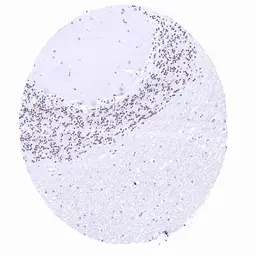

Anti-PAX6 antibody [MSVA-706M] HistoMAX™ used in IHC (Paraffin sections) (IHC-P). GTX04487

GTX04487 IHC-P Image

IHC-P analysis of human cerebellum tissue using GTX04487 PAX6 antibody [MSVA-706M] HistoMAX™.

Cerebellum with nuclear PAX6 staining of granule cells scaled.